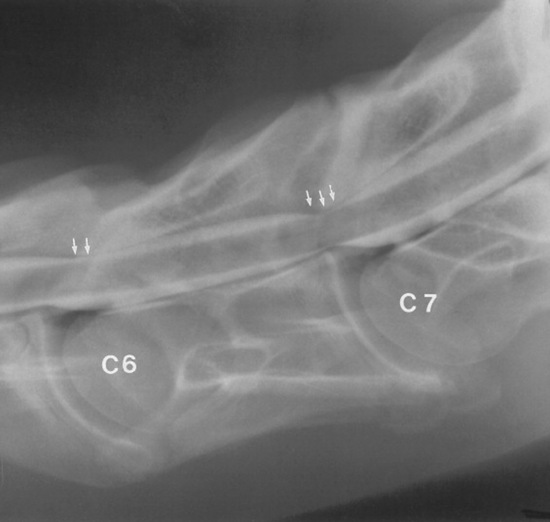

Survey radiographs of the cervical spine are obtained in standing, sedated horses. Cervical radiographs are evaluated by subjective assessment of vertebral malformation and objective determination of vertebral canal diameter.1878 The five categories of cervical malformation subjectively assessed in horses with CVSM are DJD of the articular processes, subluxation between adjacent vertebrae, flare of the caudal physis of the vertebral body, abnormal ossification patterns, and caudal extension of the dorsal laminae1878,1880 (Figs. 35-26 and 35-27). Although the presence of characteristic vertebral malformations supports the diagnosis of CVSM, subjective evaluation of survey radiographs does not reliably discriminate between horses affected and those unaffected by CVSM.1868,1878 DJD of the articular processes of the caudal cervical vertebrae is the most common and severe malformation observed in affected horses.1878 However, degenerative arthropathy occurs in 10% to 50% of nonataxic horses and is the most common and severe vertebral malformation in horses without CVSM.1869,1878 Subjective evaluation of degenerative arthropathy of the articular processes may lead to a false-positive diagnosis of CVSM.1868

Fig. 35-27 Survey radiograph of fifth and sixth cervical vertebrae. Degenerative joint disease, bony proliferation, and a facet fracture (arrows) can be seen on the articular processes of the C5-C6 articulation.

A complete myelographic examination should include neutral and stressed (flexed and extended) views of the cervical vertebrae.1863,1883 Horses with dynamic spinal cord compression show obliteration of the dorsal and ventral contrast columns during ventroflexion of the neck (Fig. 35-29), whereas spinal cord compression is not apparent with the neck in the neutral position. Static vertebral canal stenosis is characterized by constant spinal cord compression regardless of cervical position (Fig. 35-30). In some cases of static compression, ventroflexion of the neck stretches the ligamentum flavum and relieves spinal cord compression, whereas hyperextension exacerbates compression. In horses with obvious sites of spinal cord compression on neutral myelographic views, excessive flexion and extension of the neck should be avoided while obtaining dynamic views to prevent exacerbation of spinal cord injury.

Fig. 35-29 Myelographic examination of C3 through C6 with the cervical spine in ventroflexion. Dynamic instability and spinal cord compression are present at the C3-C4 and C5-C6 articulations. The ventral contrast columns are obliterated, and the dorsal contrast columns are narrowed (to less than 2 mm) at C3-C4 and C5-C6 (arrows).